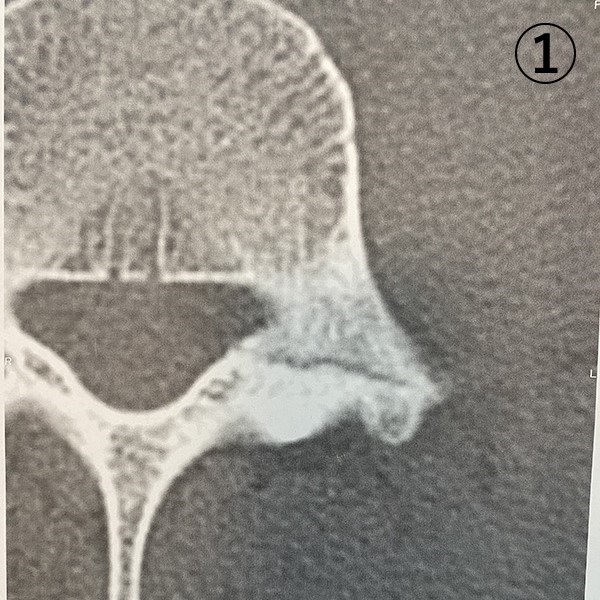

またその一か月後病院での検診で、先生が「あら、引っ付いてるねー」と不思議がるほどでCT/MRIの画像でもヒビは確認できませんでした。おかげ様で、関東大会後、春のセンバツにも間に合って晴れて甲子園でプレイすることができました。